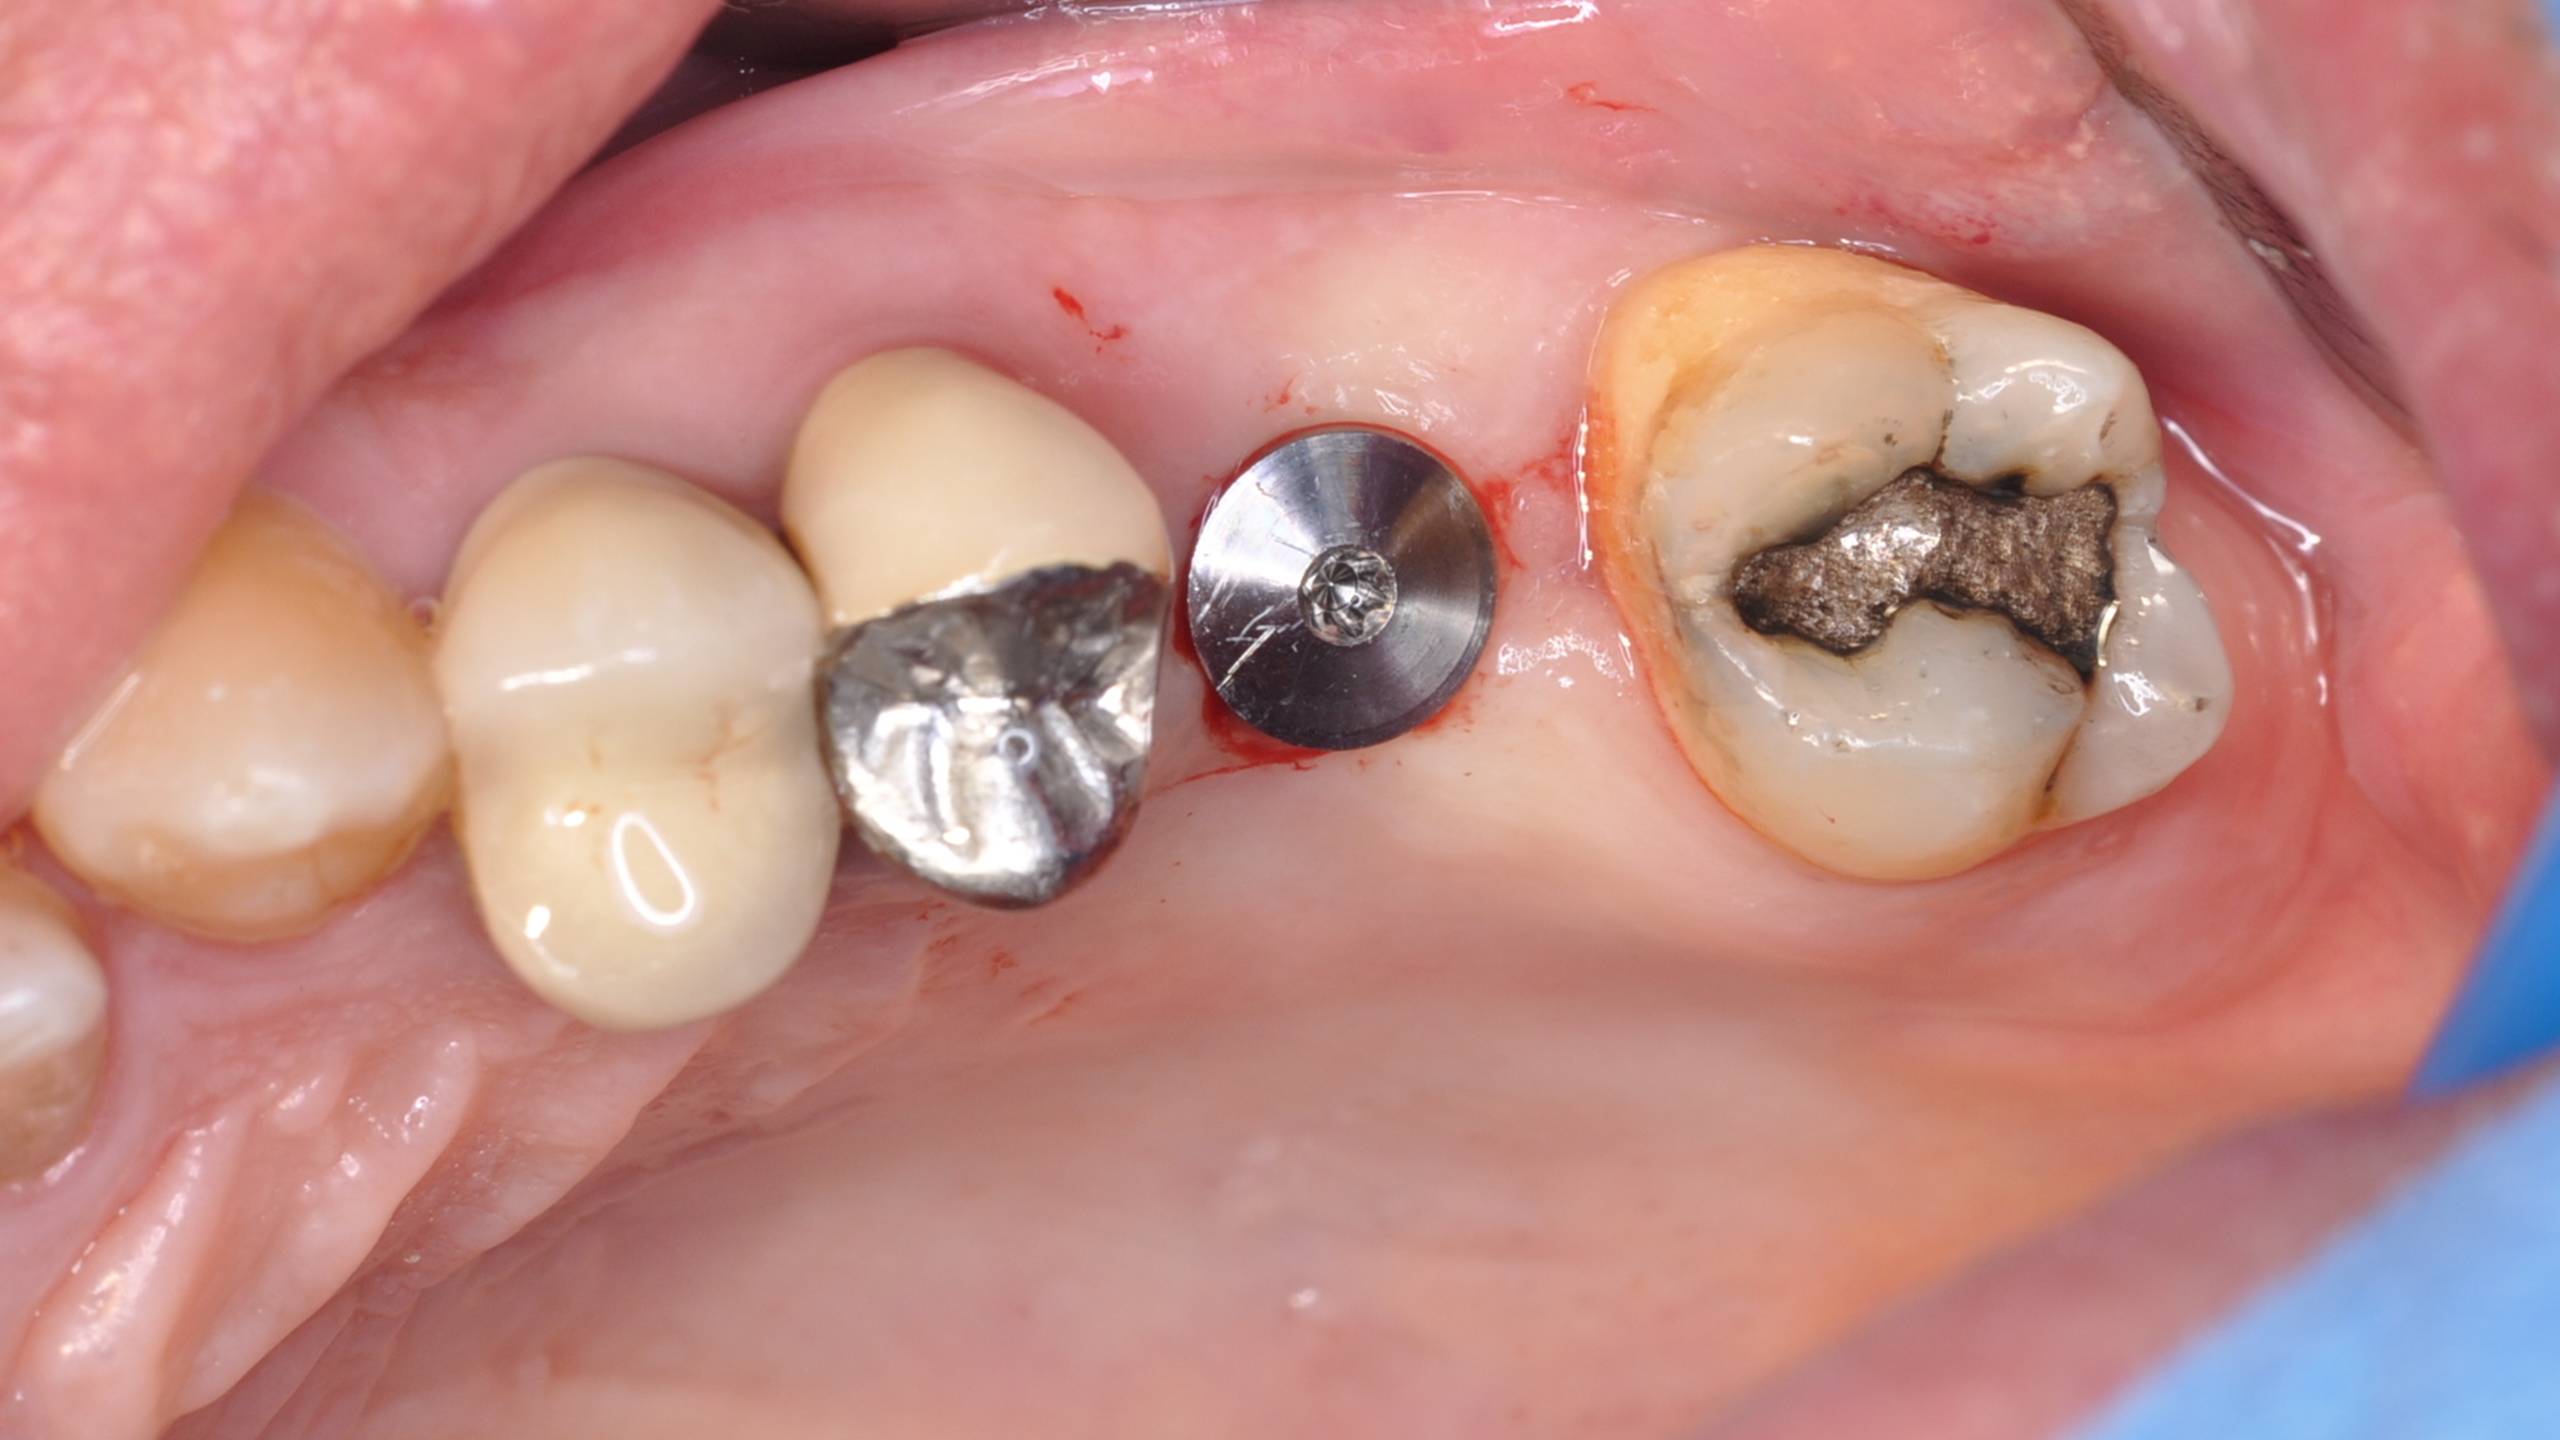

Mise en place du pilier de cicatrisation sur un Tissu Level STRAUMANN.